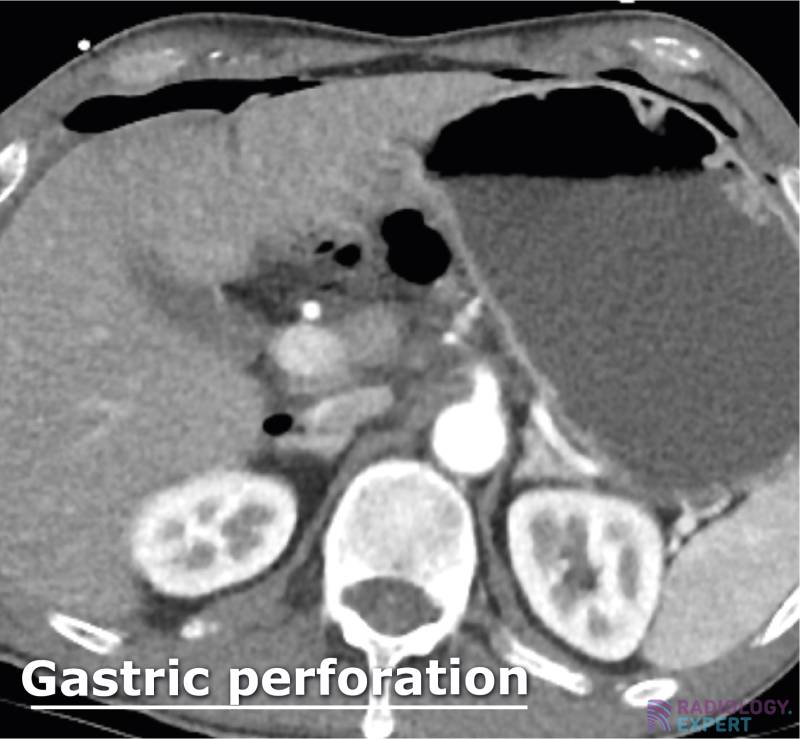

From www.radiology.expert

CT abdomen general Horse Intestinal Perforation The stomach is the most commonly affected. Ideally, cytology should be used to confirm that the horse indeed has intestinal perforation with the finding of intracellular bacteria and lysis of nucleated cells. dilation resulting from small intestinal obstruction is the most common cause. gastric rupture was identified in 8/19 (42.1%) cases, 1/19 (5.2%) had a gi and duodenal. Horse Intestinal Perforation.